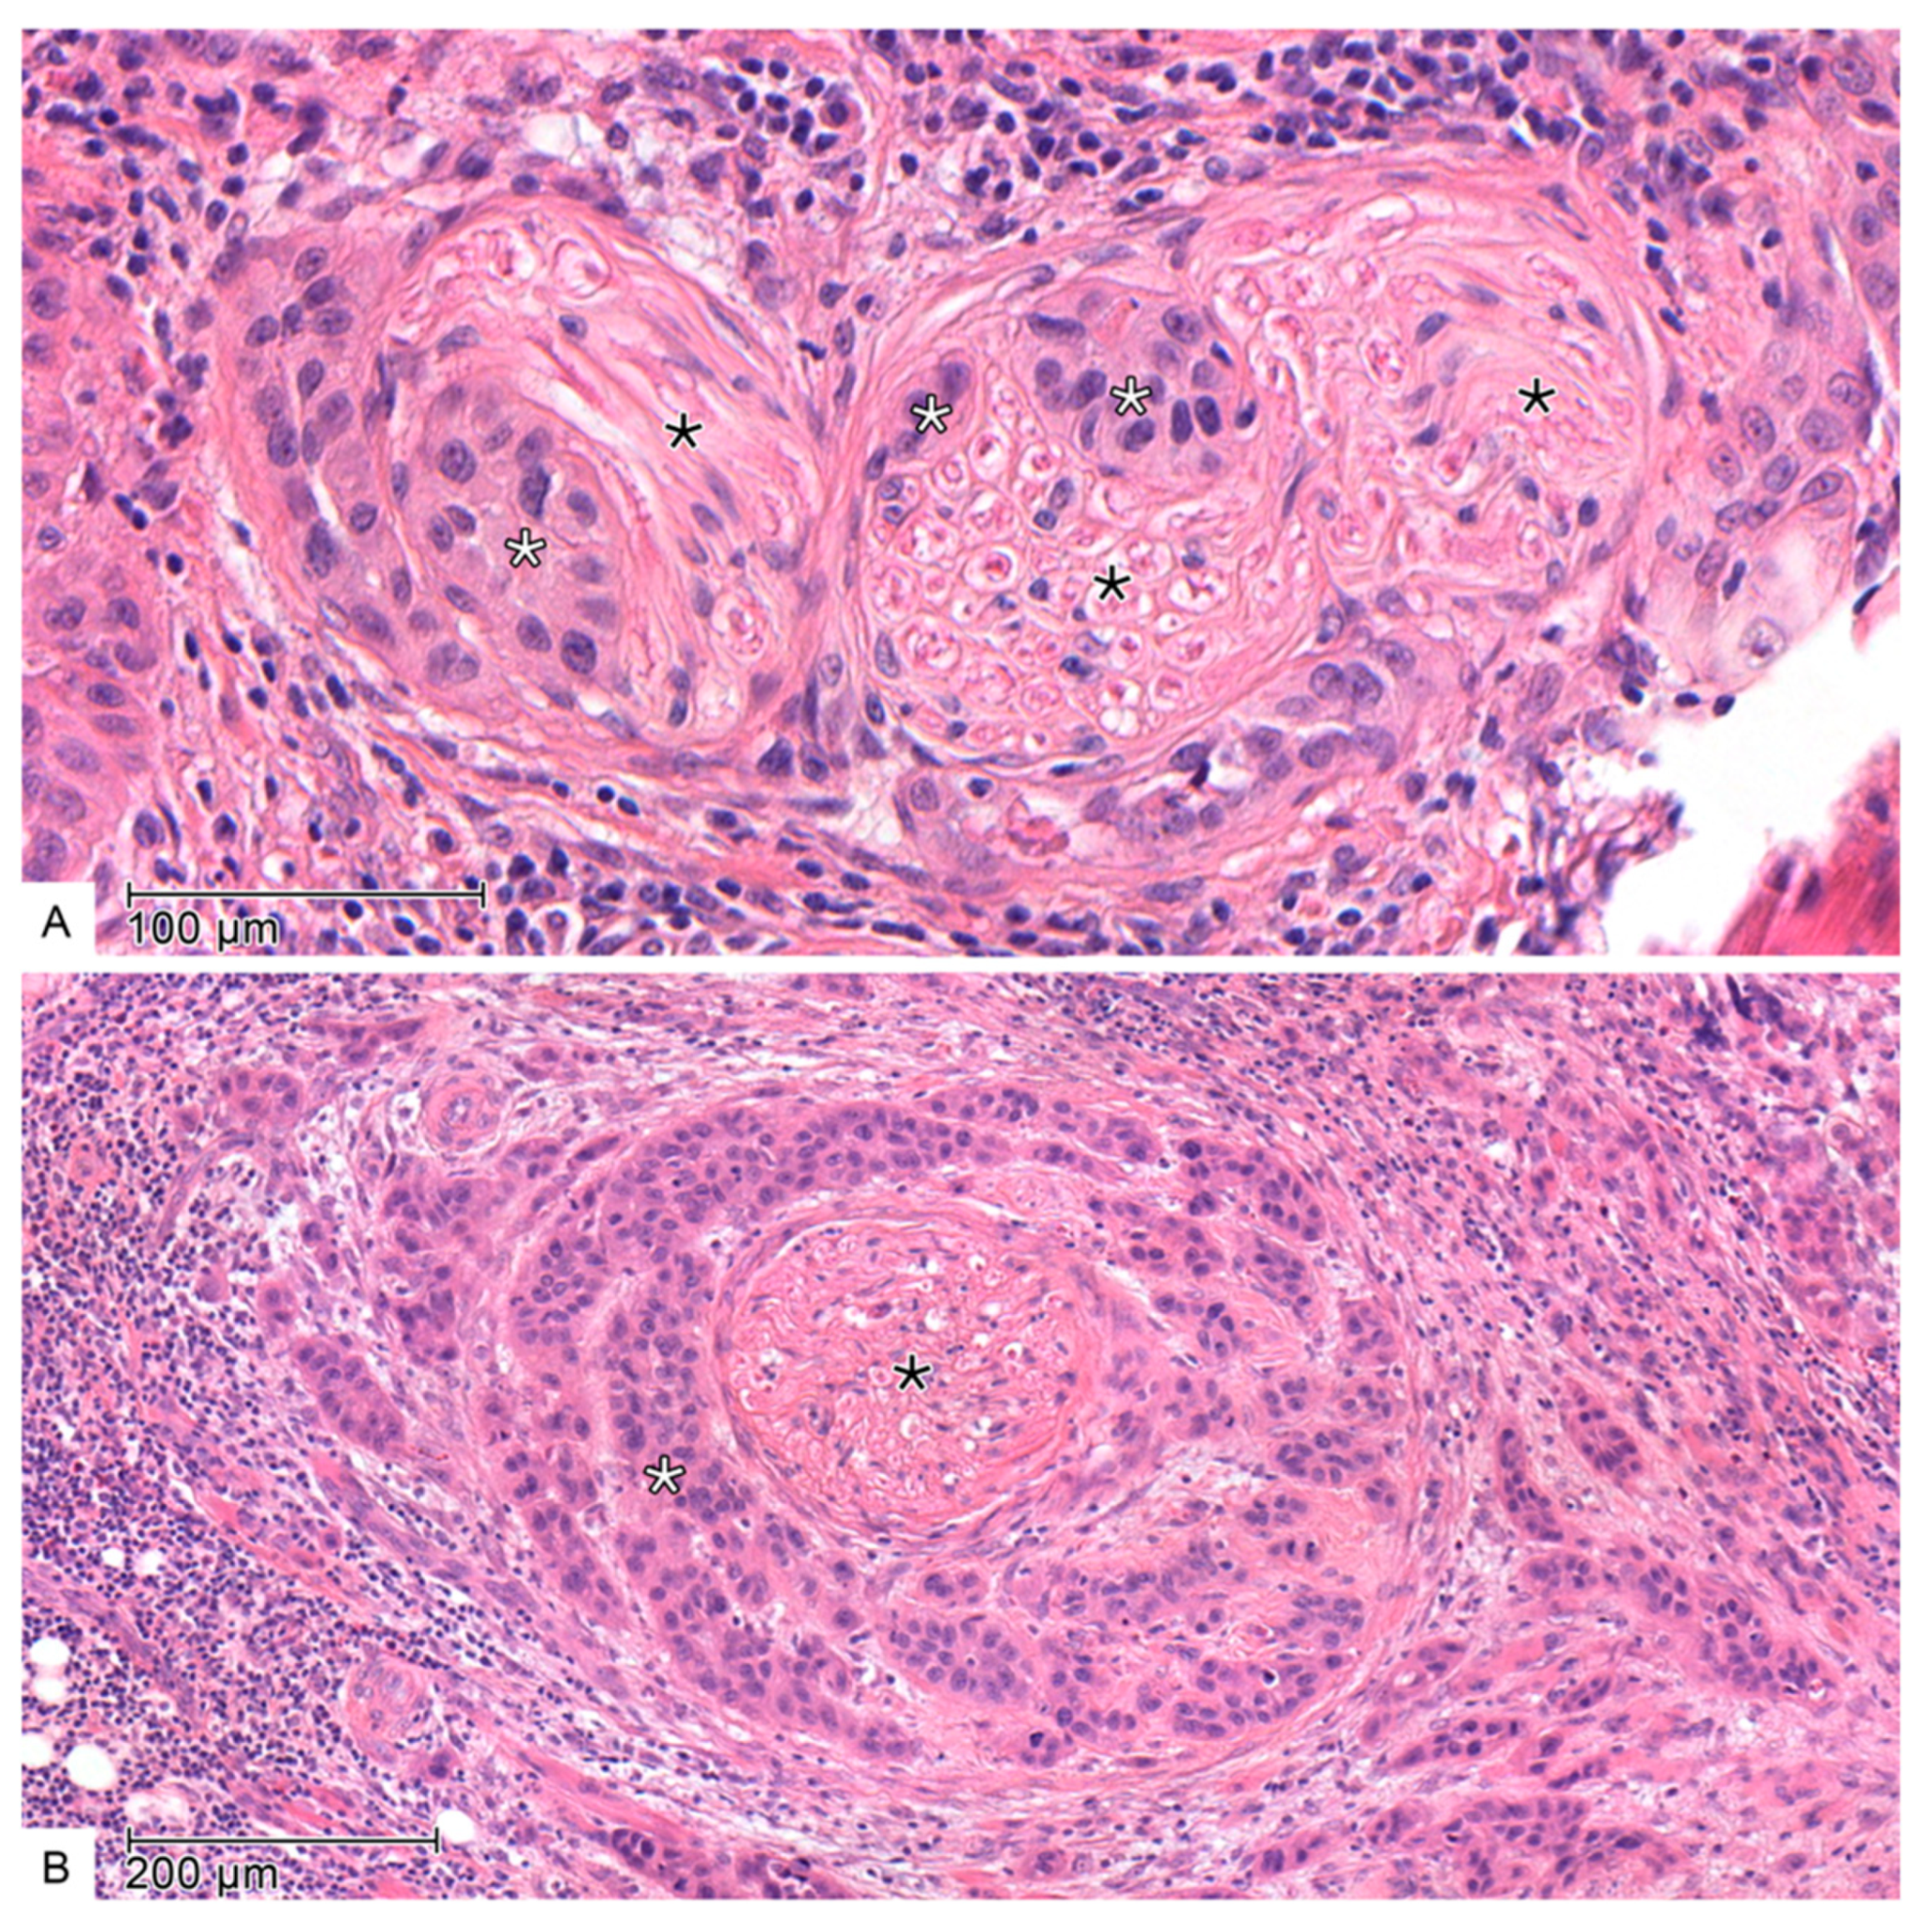

2.2. Histopathology